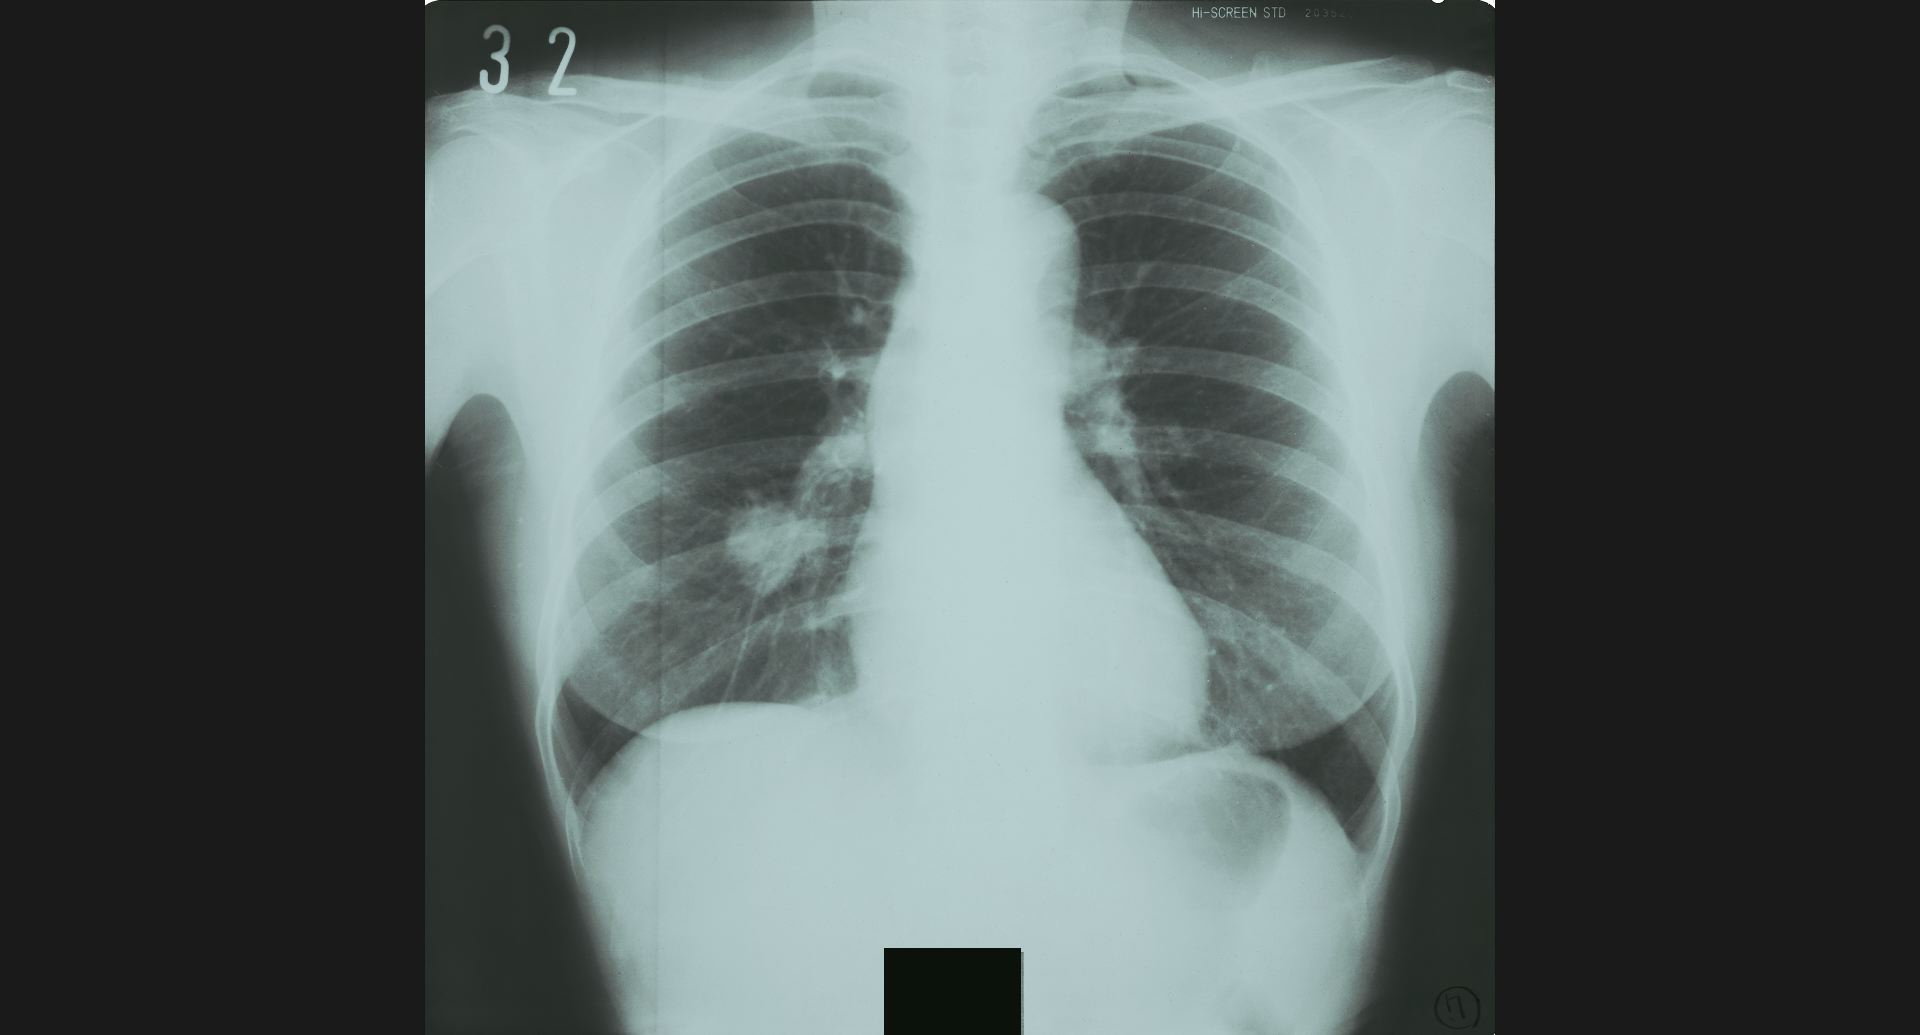

:Pneumoconiosis細かい斑状陰影。

fig.10(99KB)